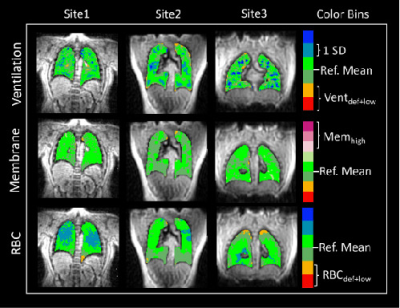

Figure 3: Representative Healthy “never-COVID-19” participants from the 3 sites. Site1 – 25 y.o. Male, Site2 – 23 y.o. Male, Site3 – 21 y.o. Male. In each image, the lungs are binned primarily to green colors, demonstrating that the use of a single reference distribution for image binning is valid across sites.